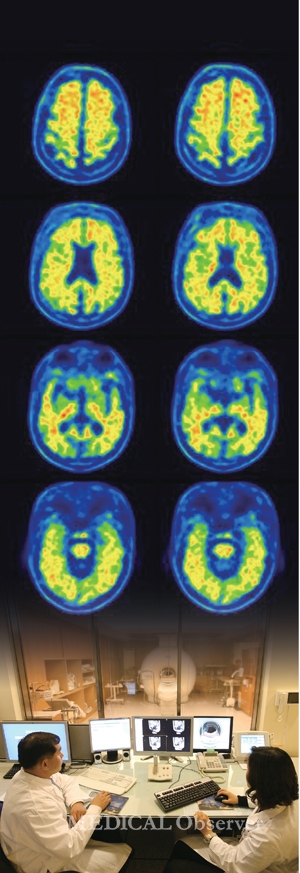

임상 증상만으로 질환을 파악하는 데 한계를 느낀 정신건강질환 진단 분야에서는 뇌 영상 기술이 새로운 대안으로 급부상했다. 컴퓨터단층촬영(CT), 자가공명영상(MRI), 기능자기공명영상(fMRI), 뇌자도(MEG) 등의 기술이 발전하면서 우울증 등 정신건강질환에 구조적 이상이 있다는 사실이 증명됐다.

우울증의 경우 변연계와 전두엽 영역에서 이상이 생겨 불면증, 식욕저하, 감정 기복 등 각종 우울 증상이 발병한다. 따라서 fMRI 등을 이용한 뇌 영상 연구가 활발한 영역이다.조현병은 우울증보다 뇌 영

상 연구가 더욱 보편화됐다. 병태생리학적 측면과 신경해부학적 측면에서 바라본 조현병 발병 원인이 그만큼 다양하기 때문이다. 조현병 환자의 뇌를 관찰한 결과, 내측두엽 등에서 회백질 용적 감소를 보였다는 연구가 다수 발표됐다.

우울증, 조현병 외에도 양극성장애 조기 진단율을 높이기 위한 뇌 영상 연구도 점차 확대되고 있다.

대표적으로 2012년 영국 킹스컬리지런던 Janaina Mourao-Miranda 교수팀은 10대 청소년 32명을 대상으로 fMRI 등을 이용해 진단의 정확성 및 유용성을 알아봤다.

그 결과 현재 양극성 장애 발병 위험이 높은 청소년부터 향후 양극성 장애 발병 위험이 상승해 치료가 필요한 청소년까지 분류했다. 정확도는 75%였다.